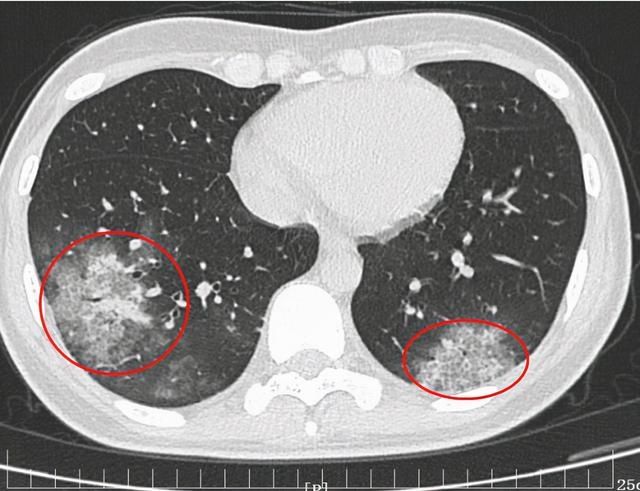

西安高新医院呼吸与危重症学科副主任医师 高和飞:“从CT上表现病人就是肺炎,收住以后发现她的肺炎和普通的肺炎还是有一定的区别,她的双肺有团片影。”

医生猜测,小张的病可能与鹦鹉接触有关。果然,在随后的病原微生物宏基因组检测中,发现了鹦鹉热衣原体 ,这是一种人畜共患的传染病。